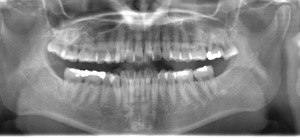

CASE 3

抜歯前

抜歯後

基本情報

| 年齢・性別 | 30代・女性 |

|---|---|

| 主訴 | 右下の親知らずが痛い 右下8 |

| 治療内容 | 通常抜歯 |

| 治療期間 | 約15分 |

| 治療費 | 約3,000円 |

| リスク・副作用 | 2〜3日は腫れと痛みがある。 |